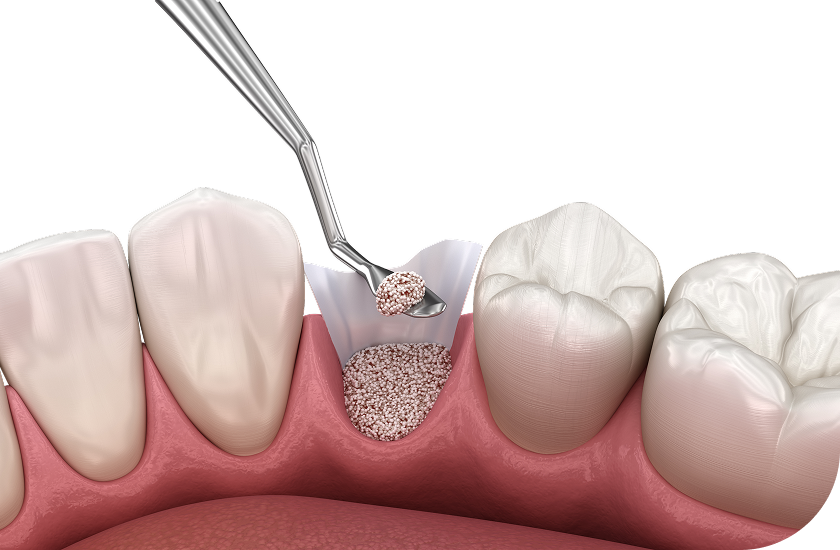

뼈이식 임플란트

임플란트에서 중요한 부분은 두꺼운 뼈와 건강한 잇몸에 있습니다.

뼈가 안 좋아 임플란트가 어려울 경우, 임플란트 식립을 위해

약해진 잇몸뼈를 이식하여 임플란트의 장기적인 수명을 향상시킵니다.

뼈이식 임플란트

성공적인 임플란트 식립을 위해서는 충분한 양과 질의 잇몸뼈가 필수적이지만,

경우에 따라 잇몸뼈가 부족한 경우가 있습니다.

이 경우 뼈이식술을 통해 먼저 잇몸뼈의 양과 질을 개선한 후

임플란트를 식립 해야 장기적인 안정성과 성공률을 높일 수 있습니다.

잇몸 뼈 소실 정도 진단

식립 할 위치에 인공뼈 이식

임플란트 식립 및 보철물 결합